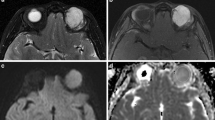

Test-retest repeatability

Repeatability of IVIM parameters in the orbital mass was good for ADC and D (mean CV 12% and 14%, ICC 95% and 93%, BA-LA : [−0.35; 0.35] and [−0.36; 0.27]) and poor for f and D*(mean CV 43% and 110%, ICC 90% and 65%, BA-LA : [−0.10; 0.10] and [−23.1; 20.9]) (Fig. 2.a). There was a significant correlation between ADC and D values in the orbital mass (p<0.001).

Inter-observer repeatability

Inter-observer repeatability was almost perfect in the orbital mass (ICC = 95%, 93%, 94% and 90% and BA-LA = [−0.30; 0.29], [−0.26 0.27], [−0.06; 0.07] and [−10.5; 8.6] for ADC, D, f and D*, respectively) (Fig. 2.b). It was almost perfect in the lacrymal gland for all the IVIM parameters (ICC = 80%, 84%, 90% and 84% and BA-LA = [−0.56; 0.44], [−32; 0.23], [−0.06; 0.10] and [−12.3; 12.1] for ADC, D, f and D*, respectively). It was almost perfect in the extra-ocular muscles and the temporal muscle for ADC, almost perfect in the lateral extra-ocular muscle and the temporal muscle for D and in the temporal muscle for f. This level of inter-observer repeatability was only seen for the extra-ocular muscles and the temporal muscle for D* (Supplementary Fig. 2). All detailed values are shown in Table 4.